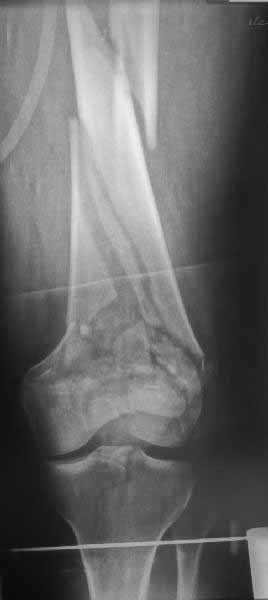

В приложении пример недавней операции, C3, открытая репозиция, фиксация мыщелков спицами и винтами, ретроградный синтез большеберцовым гвоздем 10,5 мм диаметром, винты 5 мм.

Коллеги, извиняюсь за задержку с результатом. Через медиальную артротомию обнажили н/3 бедра, отрепонировали внутренний мыщелок, затем по нему сопоставили суставную поверхность бедра с латеральным мыщелком.

Больная выписана в ортезе с регулируемым углом сгибания в колене, с рекомендациями через 3 нед. удалить спицы и начать разрабатывать сустав.

По прямому снимку репозиция удалось, поздравляю! А с латеральной стороны подозрение на флексионный компонент латерального мыщелка остается, а снимок получился косым, надо было бы повторить.

Выбор имплантов не совсем удачный, подкожно выступающие болты в мыщелках вскоре могут привести к проблемам. Вместо солитарной фиксации болтом-стяжкой дистально можно было бы добавить пару винтов, которые создали бы ротационную стабильность и межфрагментарную компрессию.

Возможно, есть скрытый замысел, неочевидный для нас - не понятны латерально оставленные спицы. Спицы возможный очаг вторичного осложнения, и, тем более у взрослых, тонкие спицы не создают адекватную фиксацию.

Djoldas,скрытого смысла в спицах нет. Без них латеральный мыщелок получается фиксированным только к медиальному, который, в свою очередь, фиксирован к проксимальному отломку. Соответственно латеральный мыщелок не фиксирован к бедру. Спицами мы попытались создать какую-никакую-стабильность латерального мыщелка относительно проксимального отломка бедра.

Болт-стяжка, на мой взгляд, создает не меньшую межфрагментарную компрессию чем винты. Не понял относительно ротационной стабильности винтов.